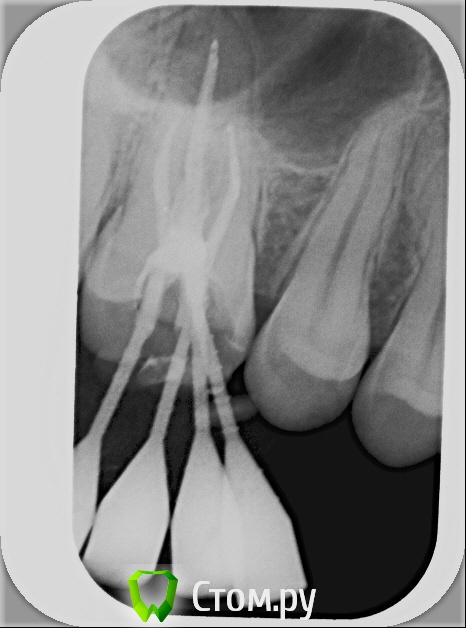

xSlon Опубликовано 13 августа, 2014 Поделиться Опубликовано 13 августа, 2014 Доброго времени суток!Прошу вашей помощи по сложному зубу, который не могут вылечить уже очень длительное время. Около 3х лет назад обнаружил, что при постукивании по 16му зубу(он был запломбирован совсем давно, не помню даже где и в каком году) появляется небольшая боль. Зуб не мешал, не доставлял беспокойств, но решив, что в таких случаях нужно действовать превентивно, пошел к стоматологу и рассказал о проблеме. Он посмотрел зуб(без вскрытия), сказал что никаких признаков боли не видит и считает что нужно удалять нерв. Поскольку зуб проблем не доставлял, я отказался.В течение этих трех лет состояние не ухудшалось, но я еще два раза ходил к разным стоматологам, описывал симптомы, они смотрели зуб, никаких признаков болезни не видели и советовали заниматься зубом когда он будет доставлять настоящие неудобства.В середине октября 2013 года ситуация ухудшилась, зуб начал периодически не сильно болеть, реагировать на холодное и горячее. В середине декабря ситуация сильно ухудшилась, зуб начал сильно болеть, сильно реагировать на холодное и горячее, сильно болеть даже при простом касании. Я обратился в стоматологию1 к врачу1, где мне вскрыли зуб, сказали что обнаружили под пломбой кариес, из-за кариеса произошло воспаление нервов и нужно удалять нервы в зубе. Боль была очень значительной, я не раздумывая согласился. Мне вскрыли зуб, поставили обезболивающее(или лекарство - точно не знаю), и сказали прийти через 7 дней, боль прошла. Через 7 дней мне обработали каналы и запломбировали Metapex'ом, сказали прийти в феврале(возможно еще удалили лекарство, точно не помню). В феврале мне за 1 посещение запломбировали постоянно каналы и за 2е посещение запломбировали зуб. К середине февраля лечение закончилось, жалоб не было. Единственное - удивляло что зуб, несмотря на удаление нервов, по старому реагирует на постукивание небольшой болью, но я не придал этому большого значения.Спустя 2 месяца, в середине апреля, остро заболел тот же самый зуб, с теми же симптомами - сильная боль, сильная реакция на холодное и горячее, сильная боль при касании. Врач1 был в отпуске, поэтому я пошел к Врачу2 в ту же самую Стоматологию1. Описал ситуацию, Врач2 посмотрела мою карточку, вскрыла зуб, осмотрела его, сказала что где-то должен быть 4й канал, но она не может его найти, сказала что вставила куда-то в зуб лекарство, сказала прийти через неделю.Боль утихла, пришел через неделю к тому же Врачу2, повторно вскрыли зуб, повторно поставили лекарство, но Врач2 сказала что 4го канала, который там должен быть, она не видит. Посоветовала обратиться к другому врачу, возможно, в другую стоматологию Через неделю, уже в начале мая, пришел повторно, запломбировали каналы Metapex'ом, поставили временную пломбу. По совету знакомых, в начале июня обратился к частному Врачу3, который специализируется на работе под микроскопом. Описал ей ситуацию, она вскрыла зуб, нашла четвертый канал, вставила туда лекарство, сказала прийти через неделю. Через неделю реакция зуба на слабые постукивания сохранилась, на приеме у Врача3 поставили более сильное лекарство(насколько я помню, с антибиотиком), прописала дополнительно в течении 5 дней пропить сильные антибиотики, сказала прийти через 10 дней. Через 10 дней, в конце июня, та же реакция зуба сохранилась. На приеме у Врача3 решили окончить лечение, потому как Врач3 на следующий день уходила в отпуск, а я, через несколько дней, уезжал в командировку. Перед отъездом пошел в Стоматологию1 к Врачу2, чтобы снять лекарство и временно запломбировать каналы и поставить временную пломбу. Врач2 сказала, что при вскрытии зуба она увидела 4й канал, попыталась определить длину канала с помощью прибора, используя самый тонкий инструмент(как я понял - это некая игла, подсоединенная к прибору, ее всовывают в канал, чем ближе кончик иглы к концу канала, тем сильнее он пищит), определить длину канала ей не удалось. Она предположила, что либо канал очень узкий, либо он изгибается, поэтому не удается дойти до конца канала.В командировке, в середине июля обновлял временную пломбу(от нее отвалился небольшой кусочек) в Стоматологии2, вкратце описал проблему Врачу4, он посоветовал использовать(дословно с листочка, который он мне дал) пломбировку материалом для к/к Forfenan Forident(резорцин-формалиновая паста). Сказал, что при таком методе, воспаленный нерв полностью обволакивается пастой, которая гермитизирует нерв, не давая разиваться воспалительному процессу. Сам воспаленный нерв остается, но организм, со временем, справляется с ним сам.Вернувшись из командировки, я пошел, по советам родственников, в Стоматологию3, к Врачу5. Описал ситуацию, сделал панорамный и прицельный снимки. Врач5, не вскрывая зуб, сказала что считает, что необходимо применить метод депофореза. Прошу вас, пожалуйста, посоветовать, каким образом вылечить этот зуб? Стоит ли попробовать резорцин-формалиновую пасту? Стоит ли делать метод депофореза? Возможно есть какие-то другие методы лечения? Прикладываю все снимки зуба из Стоматологии1Панорамный снимок из Стоматологии3, сделан 12 августа. https://yadi.sk/i/_hIqGP1IZaT4Y Ссылка на комментарий

Scrabble Опубликовано 31 августа, 2014 Поделиться Опубликовано 31 августа, 2014 Я вижу, что Вам запломбировали каналы термафилами-причём два носителя введены в дистальный, а не в мезиальный щёчный корень. В качестве силера(пасты) использовался форфенан? Если это так, то нужно всё распломбировать, полностью удалить форфенан-и ждать, пока стихнет симптоматика. Ссылка на комментарий

xSlon Опубликовано 8 сентября, 2014 Автор Поделиться Опубликовано 8 сентября, 2014 Позвонил Врачу3, проконсультировался с ней - она посчитала что ее вмешательство не нужно, имеет смысл сходить к Врачу2, просто поставить временную пломбу.Ходил 03.09.14 к Врачу2 в Стоматологию1 - сменили метапасту в небном, дистально- и медиально-щечном, медианно-небном поставили жидкость форадент, поставили временную пломбу СИЦ.Я вижу, что Вам запломбировали каналы термафилами-причём два носителя введены в дистальный, а не в мезиальный щёчный корень. В качестве силера(пасты) использовался форфенан? Если это так, то нужно всё распломбировать, полностью удалить форфенан-и ждать, пока стихнет симптоматика.Просмотрел всю карточку из Стоматологии1, слова форафен там не нашел. Скажите, пожалуйста, на каком снимке вы это увидели? Ссылка на комментарий